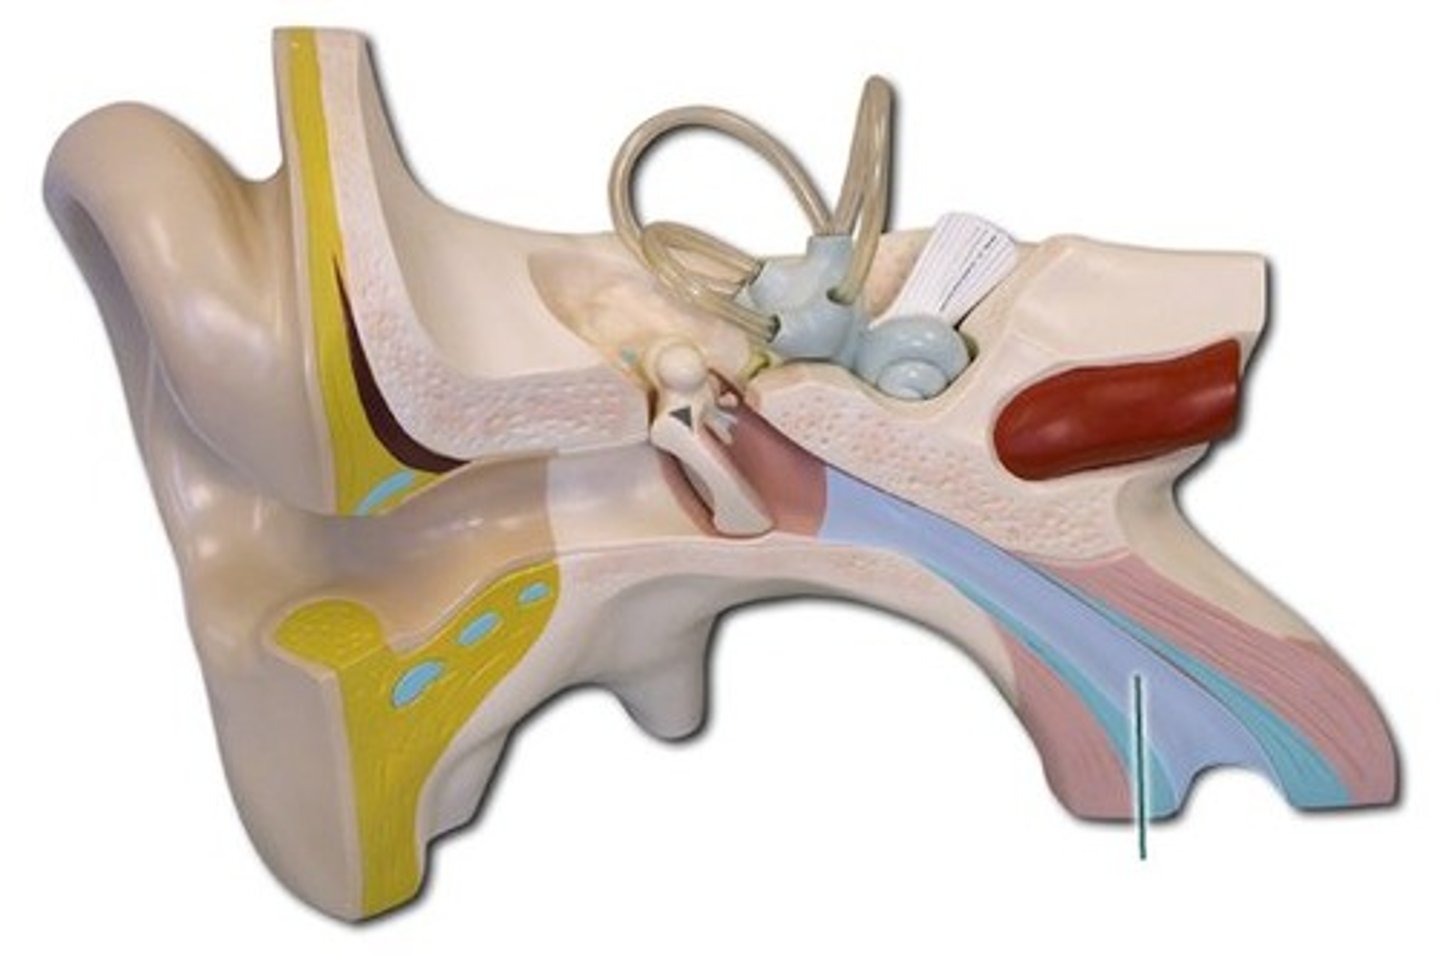

auditory tube

auricle (pinna)

cochlea

cochlear nerve

external auditory canal

incus

labyrinth (osseous + membranous)

(general structure, ignore arrow)

malleus

oval window

round window

scala tympani

section of cochlea

scala vestibuli

section of cochlea

semicircular canals

spiral organ (of corti)

section of cochlea

stapes

temporal bone

tympanic membrane

vestibular nerve

vestibule

vestibulocochlear nerve